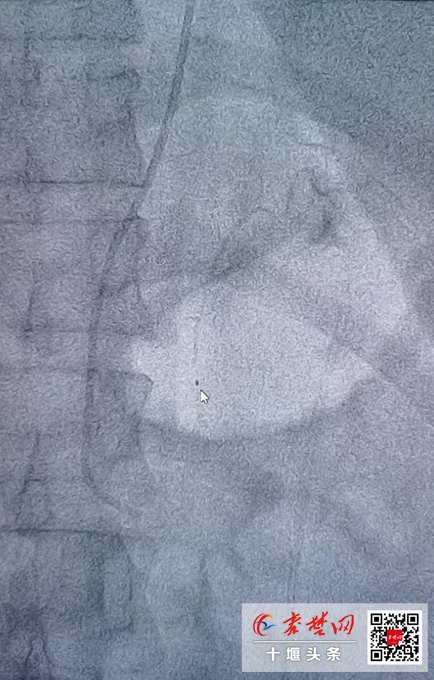

入院后,查腎上腺增強(qiáng)CT提示:雙側(cè)腎上腺結(jié)節(jié)。分側(cè)腎上腺靜脈取血(AVS)測(cè)量局部激素水平,證實(shí)夏女士為原發(fā)性醛固酮增多癥,且左側(cè)腎上腺醛固酮分泌為右側(cè)80倍,左側(cè)腎上腺為醛固酮分泌優(yōu)勢(shì)側(cè)。確定必須對(duì)左側(cè)腎上腺進(jìn)行手術(shù)治療。

術(shù)后,患者恢復(fù)良好,血壓由術(shù)前的180/106mmHg迅速降至110/70mmHg,停止補(bǔ)鉀后,多次復(fù)查血鉀均為正常水平,低鉀血癥得到治愈,復(fù)查肝腎功能也均無(wú)損傷,醛固酮水平明顯降低,大大減少患者心、腦、腎等器官損害,手術(shù)取得十分滿(mǎn)意的效果。